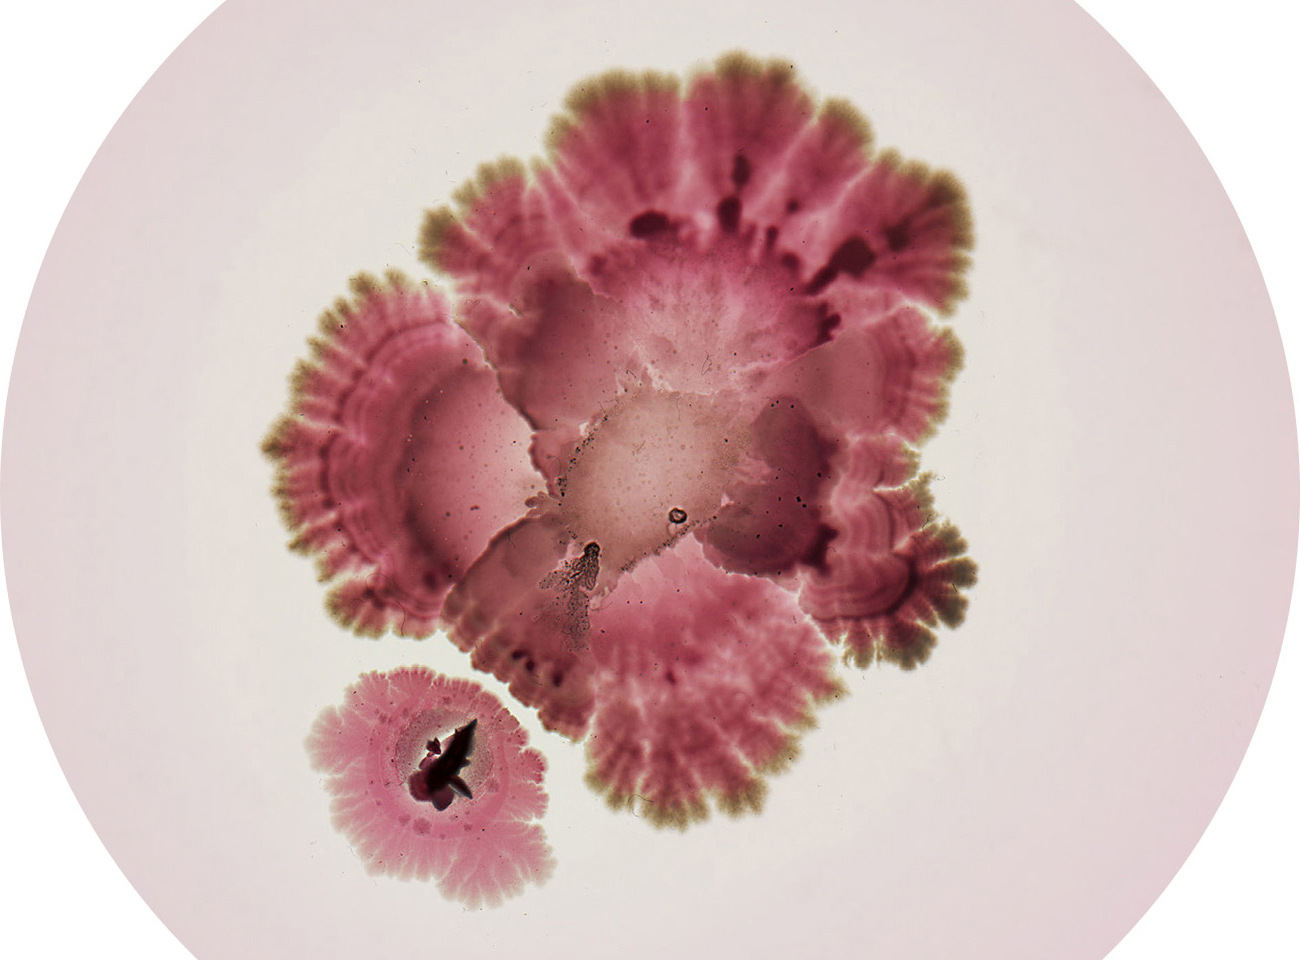

bacteria

bacteria

bacteria